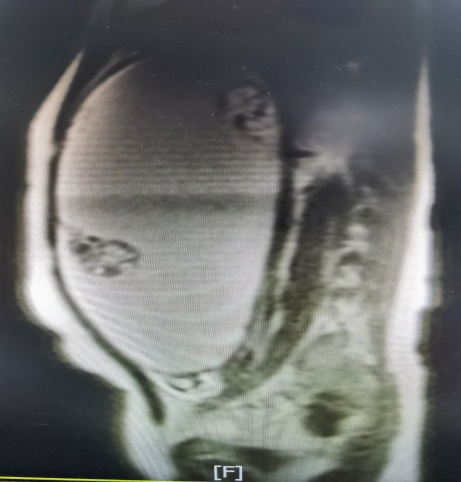

病例一:13岁女孩小瑜(化名),因“下腹痛10余天”由县医院转至我院。体格检查提示患者盆腹腔肿物约如孕8月子宫大小,肿物上界达剑突下CT提示右侧附件巨大囊实性占位(35.3cm×23.6cm×13.8cm),肿瘤标志物不高。省医派驻专家陈观娣主任带领妇科团队进行细致的查房和评估后,考虑小瑜年纪小,如果按传统剖腹探查手术术口可能长达十几厘米,术后恢复时间长,且手术疤痕的形成,影响了腹部的美观,可能对小瑜造成心理负担,遂决定行经腹小切口卵巢囊肿剥除术。

术前磁共振检查